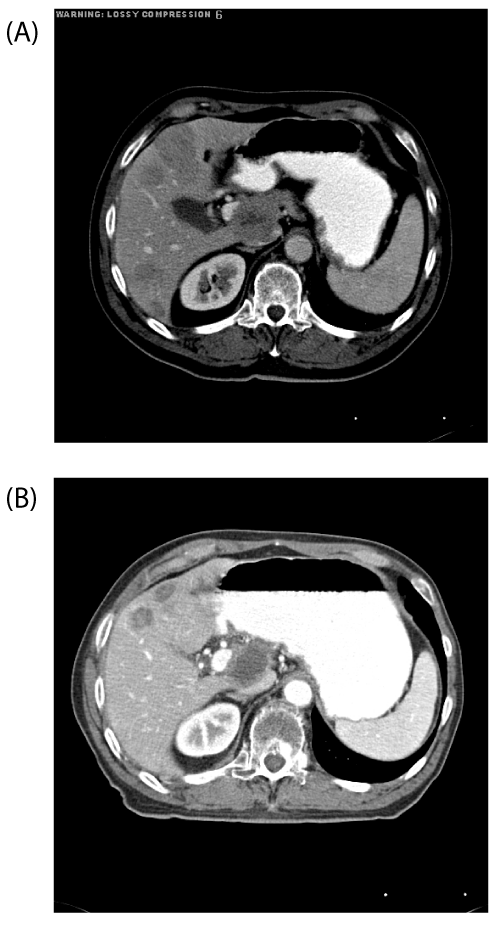

| Figure 3: A. Pretreatment diagnostic CT axial image of the patient in Figure 2. B. Post-treatment diagnostic CT axial image of the same patient at the same portion of the liver at 9 months after 90Y microsphere therapy, scored as a RECIST partial responder although no enhancement or lesion growth was ever seen in follow up. The software-estimated tumor dose was 86.6 Gy and normal liver was only 16.5 Gy; MIRD estimate was 43.7 Gy. The total activity delivered was 2.0 GBq, with tumor volume of 296.8 cc and normal liver 2109.3 cc. This patient did not experience any grade 1-3 toxicities. |